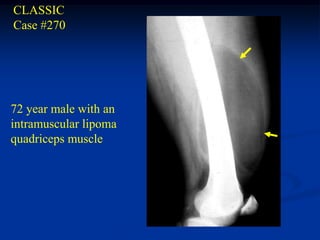

CLASSIC Case #270 72 yearmale with an intramuscular lipoma quadriceps muscle